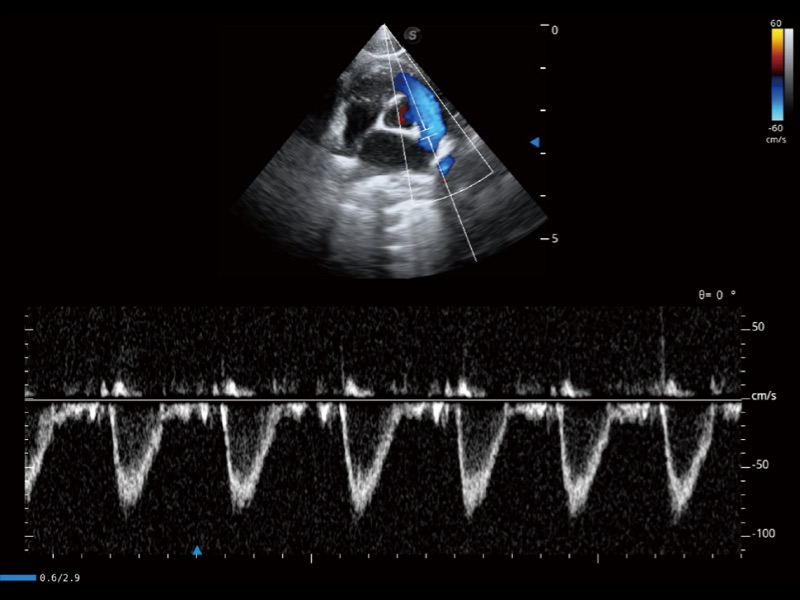

能够基于左心室壁追踪和辛普森法,自动计算射血分数,支持多个可移动点描迹,与手动测量相比,极大节省了动物医生的时间和精力。

当心脏测量结果超出正常范围时,可实时预警提示动物医生,减少疾病漏诊概率。